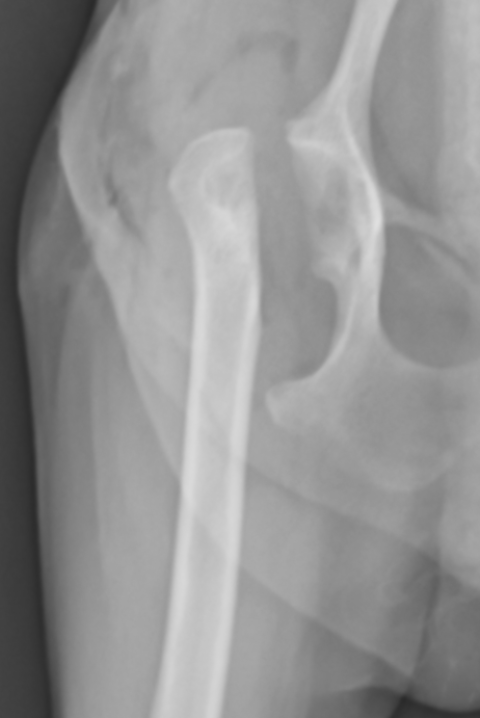

同じ症例ではありませんが、骨頭を切除した症例をご紹介します。症例は8ヶ月のトイプードルで、最近足をあげるということで来院されました。触診では足を伸ばすときに痛がり、レントゲンで骨頭の骨折が認められました。おそらく生まれつきレッグペルテスという病気があり骨頭が折れてしまったのではないかと予想されます。レッグペルテス(=大腿骨頭壊死症)とは主に小型犬種において発生する大腿骨頭の非炎症性無菌性壊死です。犬では生後数ヶ月から1年までに痛みや跛行を主訴に来院されます。原因は大腿骨に栄養が行く血管がうまく発達せず、骨頭の一部が壊死ししてしまうと考えられています。遺伝性と考えられていますが、まだはっきりとしたことはわかっていません。猫でも似たような病態があると最近言われ始めています。

骨頭の一部が折れて潰れてしまっています。